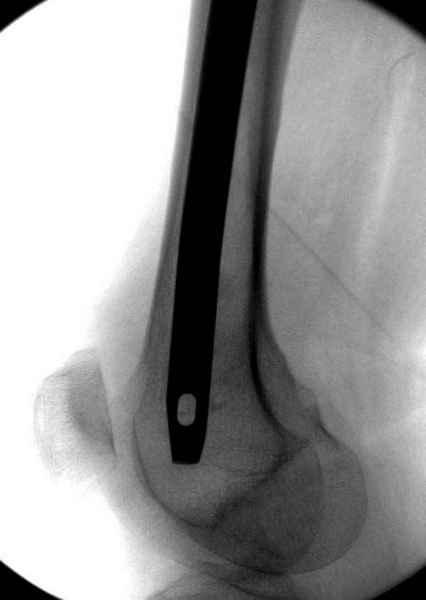

Правильно, ситуация изменилась, как говорят у нас теперь "different animal", надо решать проблему подвертельного перелома. При наличии различных вариантов фиксаторов, включая Страйкер Гамма 3, мы выбрали DePuy Antegrade Trachanteric Nail из-за многовариантности проксимальной фиксации и двойного изгиба. Вводится через вертел под 8 градусным углом, и есть достаточный передний диафизарный изгиб, предупреждающий пенетрацию дистального переднего кортекса.

На второй день после выписки упал дома. Снимки приложены. Коллеги рекомендуют удаление шурупа и вытяжение. Что делать?